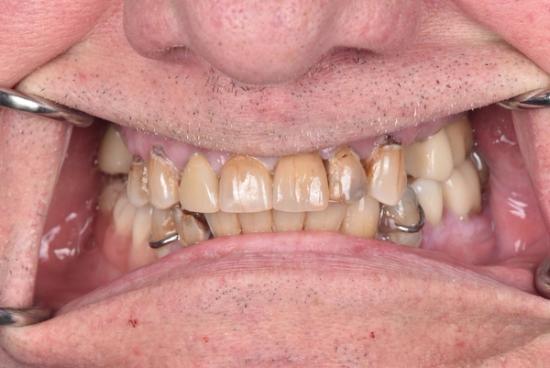

After Photo